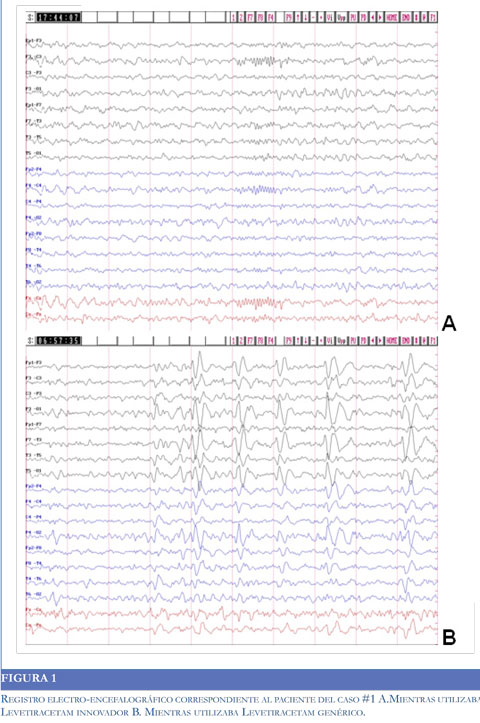

Paciente de 25 años, masculino, con diagnóstico de epilepsia focal sintomática y segundo año de postoperatorio de lobectomía temporal izquierda. Manejado con carbamazepina 2 gr/día, levetiracetam innovador 3 gr/día y lamotrigina 400 mg/día. El paciente presentaba aceptable control de crisis con este régimen terapéutico. Paciente cambia a levetiracetam genérico, posterior al cambio presenta crisis parciales complejas de automatismos manuales sin atonía, al examen físico no se encuentran alteraciones, se tomó electroencefalograma durante la utilización de medicamento genérico que mostró descargas casi continuas de POL de 2hz hemisféricas izquierdas, contrasta con EEG tomado durante el manejo con levetiracetam innovador que mostró una única descarga focal izquierda de 4 segundos (Figura 1).

Paciente de 41 años, masculino, con diagnóstico de epilepsia focal sintomática refractaria, manejado con levetiracetam innovador 3 gr/día y Fenitoína 300 mg/día. Paciente asintomático durante 9 meses, posteriomente inició levetiracetam genérico, en 3 meses de tratamiento ha presentado 5 crisis. Al examen físico no presenta alteraciones. Un EEG tomado mientras se utilizaba el medicamento innovador se encontró dentro de límites normales, un EEG tomado mientras se utilizaba el medicamento genérico mostró mala modulación de ritmos de fondo con frecuentes descargas punta-onda-aguda fronto-temporales derechas.